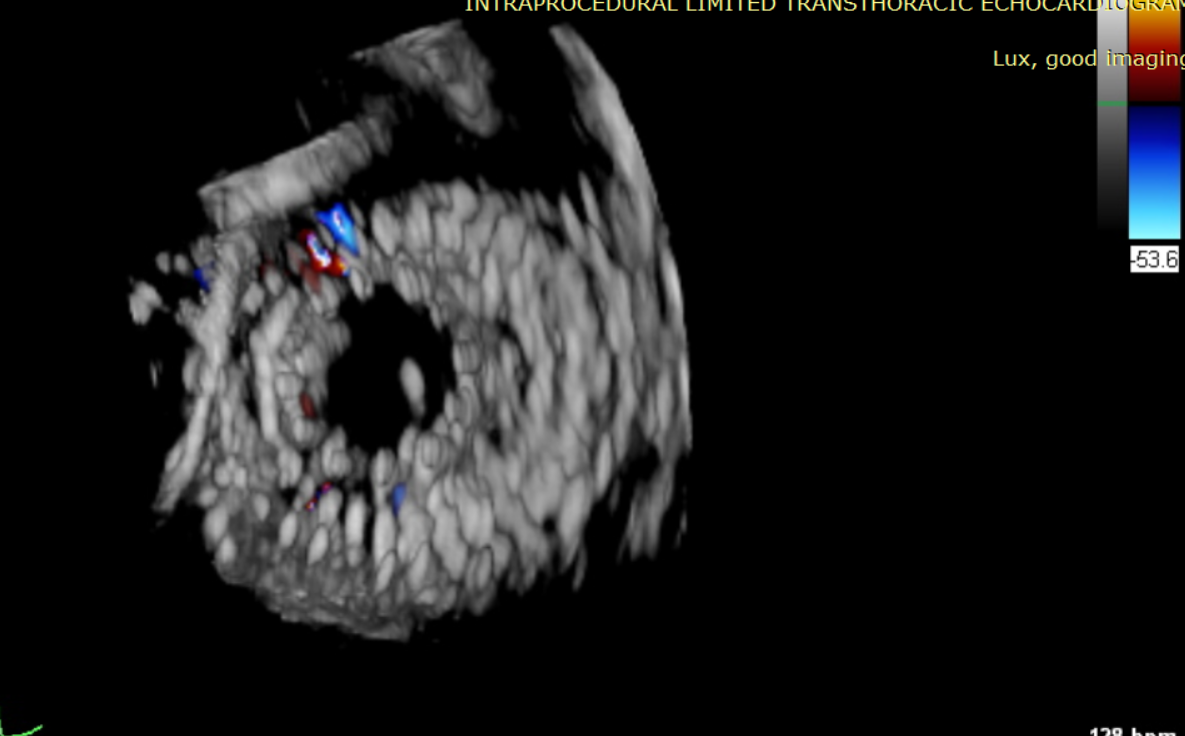

術后超聲提示無瓣周漏

術后超聲提示僅殘余輕微瓣周漏

術后Azeem Latib教授對LuX-Valve Plus經血管三尖瓣置換系統的器械性能和治療效果大為稱贊,并且認為LuX-Valve Plus的手術體驗非常好。從治療效果來看,術后即刻超聲顯示三尖瓣反流幾乎完全消失,血流動力學改善顯著,患者恢復快。在面對復雜解剖結構、超聲影像質量不佳、有起搏導線干擾時,Lux-Valve Plus也體現了極強的適應性。Thomas Modine教授參與了術中指導,他同樣再次肯定了LuX-Valve Plus術中操作的便捷性,認為LuX-Valve Plus容錯率高,對術中影像的依賴小,并表達了后期希望可以更多地應用LuX-Valve Plus三尖瓣置換系統于臨床實踐,讓更多的三尖瓣重度反流患者盡早獲益,改善預后。